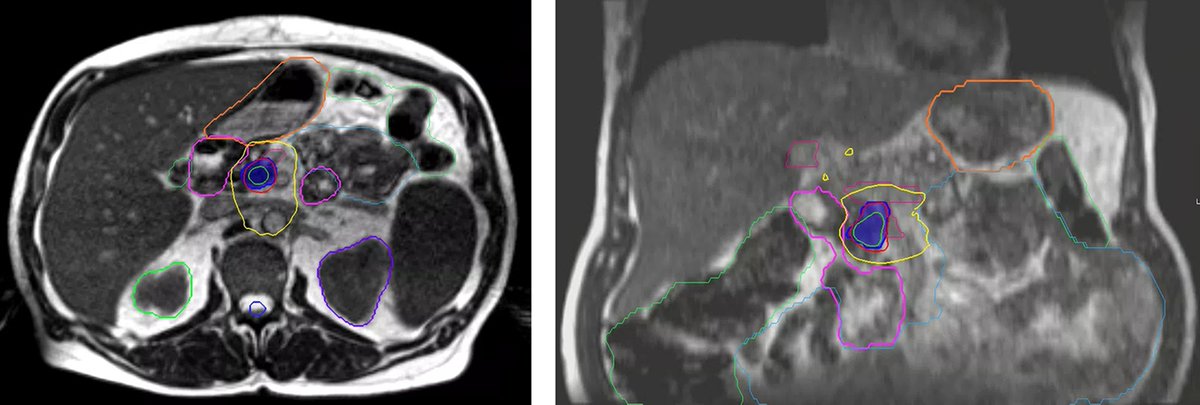

Portal Vein Stenosis Following Neoadjuvant Therapy With MRgART and Surgery for Pancreatic Cancer: A Case Report 🔗 ow.ly/YMrt50XkIq7 #RadOnc #RadOncEd #CaseStudy #RadiationOncology

Applied_RadOnc's tweet image. Portal Vein Stenosis Following Neoadjuvant Therapy With MRgART and Surgery for Pancreatic Cancer: A Case Report